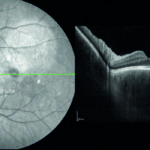

Una cefalea da indagare: diagnosi di sindrome di Vogt Koyanagi Harada